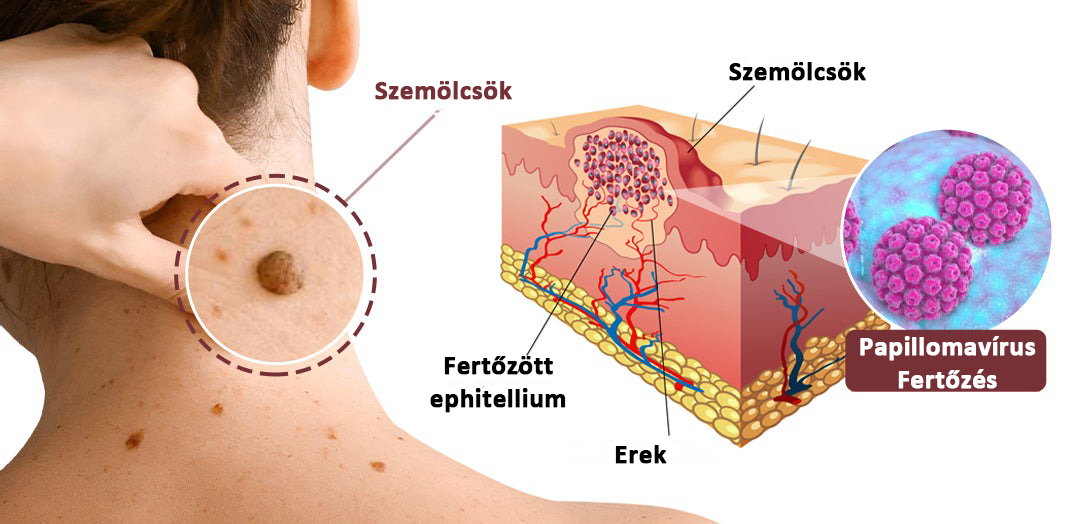

Bőrkinövések, szemölcsök, apró dudorok és érdes foltok gyakran akkor alakulnak ki, amikor a bőr a következő tüneteket tapasztalja:

Bőrkinövések, szemölcsök, apró dudorok és érdes foltok gyakran akkor alakulnak ki, amikor a bőr a következő tüneteket tapasztalja:

• Mély keratinlerakódás

• Enyhe bőrvastagodás súrlódás miatt

• Krónikus szárazság és irritáció

• A kollagéntermelés lassulása az életkorral

• Pigmentlerakódás a sérült szövetek körül

Ezek a változások kiemelkedő, érdes, sötétebb területeket hoznak létre – különösen a nyakon, a hónaljban, a mellkason, az arcon és a test redőiben.

Hogyan hat a Biancat® KeraErase a kiváltó okokra?

Az aktív botanikai komplex felszívódik a hámrétegbe, elérve a mélyebb rétegeket, ahol a dudorok és a keratin felhalmozódása elkezdődik.

A KeraErase kettős hatású megújító hatású:

① Lágyítja és lebontja a megkeményedett keratint

A tuja + teafa + ricinusolaj fokozatosan fellazítja a megvastagodott szöveteket.

② Javítja a bőr megújulását és csökkenti a lerakódásokat

Segíti a bőrt a durva rétegek természetes eltávolításában.

③ Világosítja a környező sötét foltokat

A rizskorpa + niacinamid csökkenti a pigmentációt.

As A hatóanyagok mélyebbre hatolnak, fellazítják a lerakódásokat és támogatják az egészséges bőrregenerációt.

As A hatóanyagok mélyebbre hatolnak, fellazítják a lerakódásokat és támogatják az egészséges bőrregenerációt.